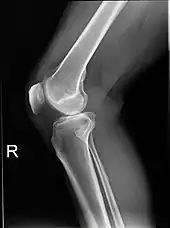

Projectional radiographs

Projectional radiography is the practice of producing two-dimensional images using X-ray radiation. Bones contain a high concentration of calcium, which, due to its relatively high atomic number, absorbs X-rays efficiently. This reduces the amount of X-rays reaching the detector in the shadow of the bones, making them clearly visible on the radiograph. The lungs and trapped gas also show up clearly because of lower absorption compared to tissue, while differences between tissue types are harder to see.

Projectional radiographs are useful in the detection of pathology of the skeletal system as well as for detecting some disease processes in soft tissue. Some notable examples are the very common chest X-ray, which can be used to identify lung diseases such as pneumonia, lung cancer, or pulmonary edema, and the abdominal x-ray, which can detect bowel (or intestinal) obstruction, free air (from visceral perforations), and free fluid (in ascites). X-rays may also be used to detect pathology such as gallstones (which are rarely radiopaque) or kidney stones which are often (but not always) visible. Traditional plain X-rays are less useful in the imaging of soft tissues such as the brain or muscle. One area where projectional radiographs are used extensively is in evaluating how an orthopedic implant, such as a knee, hip or shoulder replacement, is situated in the body with respect to the surrounding bone. This can be assessed in two dimensions from plain radiographs, or it can be assessed in three dimensions if a technique called '2D to 3D registration' is used. This technique purportedly negates projection errors associated with evaluating implant position from plain radiographs.[104]